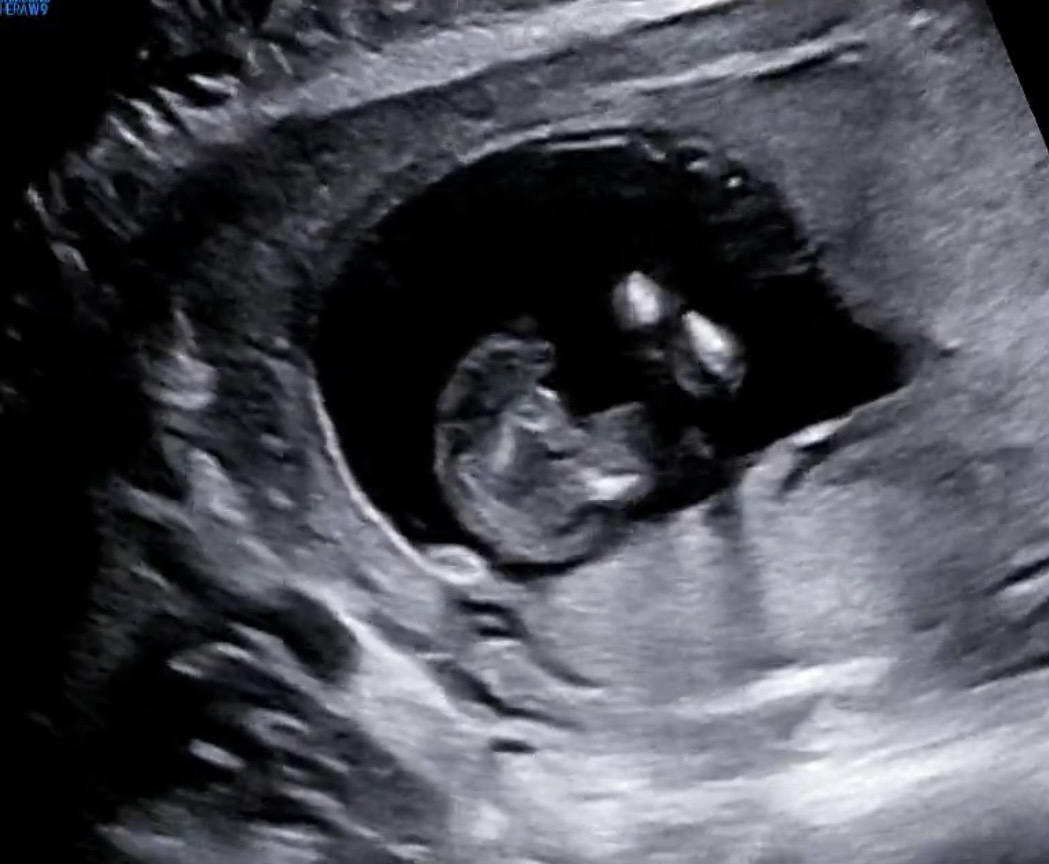

성별 나왔어요 ☺️

14w2d 매끈~한 다리사이 ㅎ 딸이랍니다 태몽이 다 용꿈 멧돼지꿈 황소꿈 이런거여서 아들인가 싶었는데 딸이라네요 남편이 장손에 외동이라 제가 아들을 바란것도 있었고 남편보다는 저를 닮길 바라는 마음도 있어서 첫째는 아들이길 했는데 딸 당첨! 그래도 첫째 딸 너무 귀하고 앞으로가 기대되네요 ㅎㅎ 딸아 엄마 닮으렴… 간절히 빈다 💗

12주에 보러 갔는데 애기가 엎드려있어서 궁댕이만 실컷 보고 왔었어요 😅 각도법도 안보여주고 애태우다가 오늘은 다리사이 촘파 보자마자 꼬고 있던 다리를 싸악 풀어줘서 확인했네요 ㅎㅎ